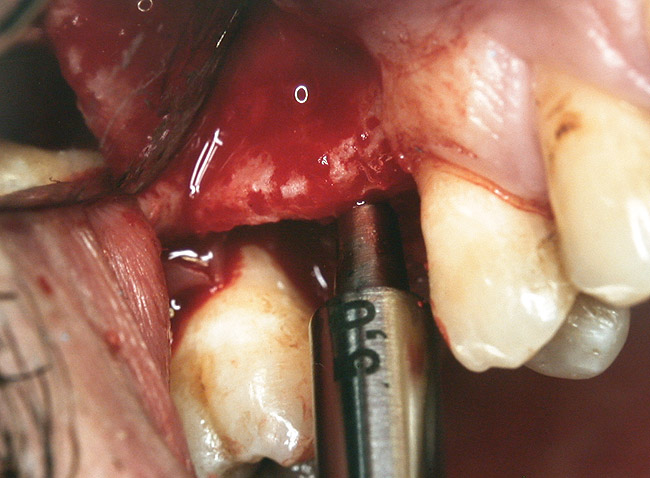

At the time of surgery, the tooth was extracted without harvesting any mucosal flap because the implant site was prepared by means of a pilot drill bur (Figure 13) and alternating osteotomes (Figure 14A and Figure 14B). The implant was positioned and showed primary stability. The implant was loaded 2 days after surgery. Then, splinted PFM crowns supported by custom gold abutments were delivered. At 6 months posttreatment, the radiograph revealed no bone resorption and the clinical result was optimal (Figure 15A and Figure 15B).

Figure 14a  Alternating osteotomes were used to prepare the implant site.

Figure 14a

Figure 14b  Alternating osteotomes were used to prepare the implant site.

Figure 14b